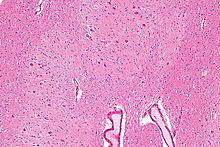

Micrograph of the dentate nucleus (pale pink). H&E stain.

The architecture of cerebellum has a form that resembles the structure of a crystal, so a slice anywhere in the cerebellum gives repeated architecture. The eight cerebellar nuclei, located within the deep white matter of each cerebellar hemisphere, are grouped into pairs, with one of each pair in each of the two hemispheres. As a chunk of tissue, the dentate nucleus with overlying cerebellar cortex makes up a functional unit called the cerebrocerebellum. Thus, there is a part of cerebellum that communicates exclusively with the dentate nucleus.[4]